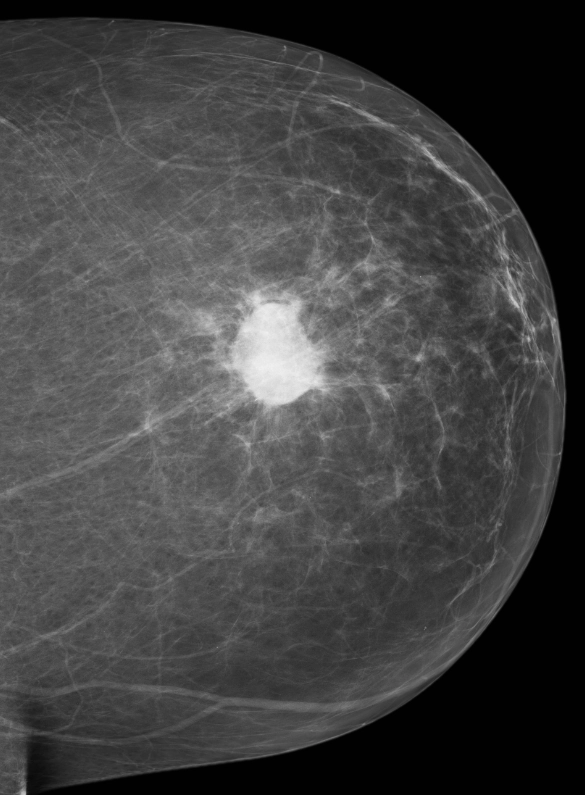

Ung thư biểu mô tuyến vú xâm nhập loại không đặc biệt (Invasive breast carcinoma of no special type)